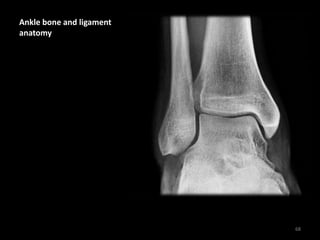

Ankle bone and ligament

anatomy

The ankle is stabilised by

multiple ligaments not

visible with X-ray